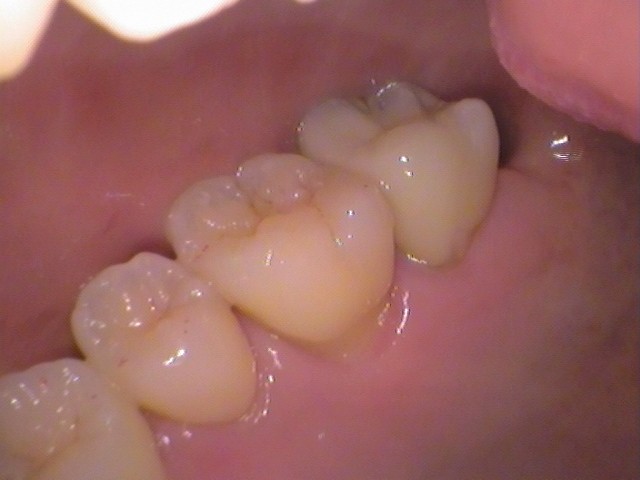

レジンの中で虫歯が進行している?20代女性。

• Before

After